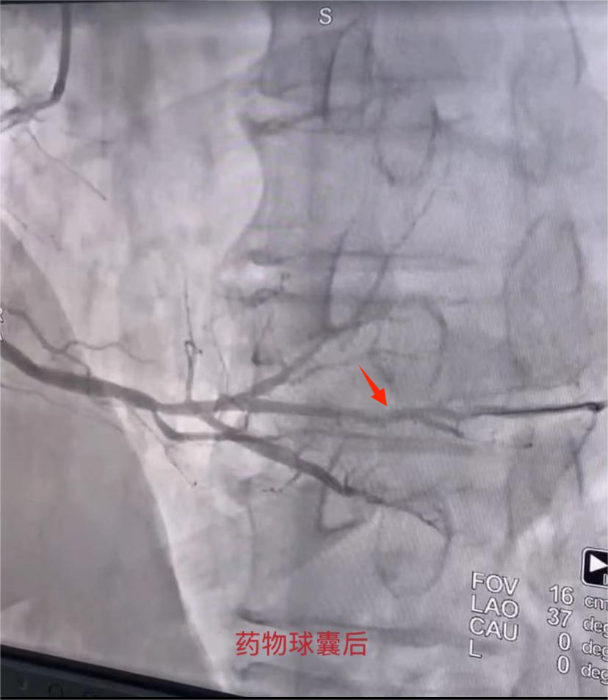

爲進一步明确病因,心血管病院二病區副主任張偉傑及醫生(shēng)馬玉娥行冠脈造影(yǐng)檢查,術(shù)中造影(yǐng)提示:右冠遠(yuǎn)端90%狹窄。張偉傑考慮狹窄部位屬于遠(yuǎn)端小血管病變,無相(xiàng)應支架可(kě)選,遂決定在病變部位給予藥物球囊治療。手術(shù)成功結束,張某再無心絞痛發作(zuò)。